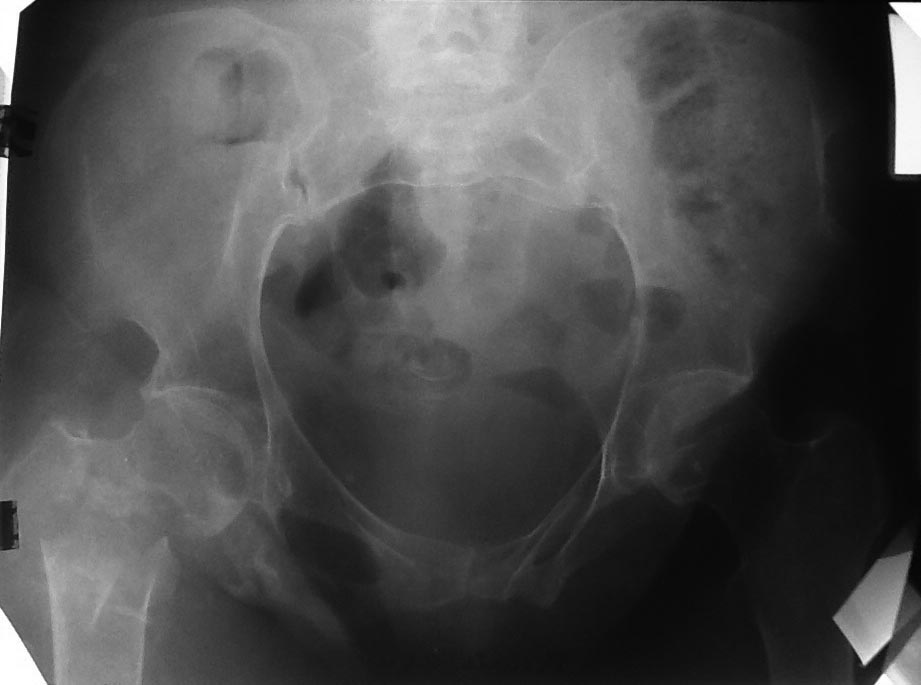

Пациентка 47 лет, нижняя параплегия, "колясочница"', но достаточно

активна - самостоятельно себя обслуживает- моется в ванной, готовит и т.

д. Спинальная травма у пациентки более 20 лет назад. Чувствительность до

колен сохранена. В 90-х годах был выполнен

остеосинтез диафизарных переломов бедра и голени с противоположность

стороны пластинками. Зажив летние ран без осложнений. У нас вызывает

сомнение в синтезе из-за низкого качества кости, к тому же пациентка

"колясочница". Может кто-то имеет опыт в лечении таких пациентов.